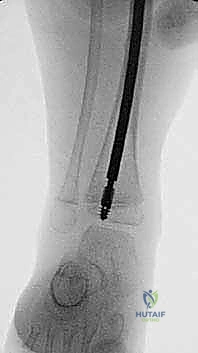

الدليل التفصيلي لخطوات العملية الجراحية: بضع العظم عبر الجلد والمسامير التلسكوبية

تُعد هذه العملية من أدق العمليات في جراحة عظام الأطفال، وتتطلب مهارة استثنائية كما هو الحال مع البروفيسور محمد هطيف. يتكون المسمار التلسكوبي (Fassier-Duval) من جزأين يتداخلان ببعضهما البعض (مثل التلسكوب). يتم تثبيت أحد الأطراف في أعلى العظم والطرف الآخر في أسفله. عندما ينمو العظم، ينزلق الجزء الداخلي من المسمار للخارج، مما يسمح للعظم بالنمو الطبيعي دون أن ينثني أو ينكسر.

الخطوة الرابعة: إدخال المسمار التلسكوبي

بعد تقويم العظم وجعله مستقيماً كحبات المسبحة على خيط، يتم إدخال السلك الدليلي (Guide Wire). ثم يتم إدخال الجزء الخارجي (الأنثوي) من المسمار التلسكوبي وتثبيته في الجزء العلوي من العظم (Epiphysis).

بعد ذلك، يتم إدخال الجزء الداخلي (الذكري) من المسمار عبر الجزء السفلي من العظم وتثبيته في المشاشة السفلية. هذا التصميم العبقري يضمن حماية العظم بالكامل من الداخل.

الخطوة الخامسة: الإغلاق والتجبير

نظراً لأن التدخل كان عبر ثقوب صغيرة، يتم إغلاقها بغرزة واحدة أو حتى بشريط لاصق طبي. يتم وضع جبيرة خفيفة أو دعامة لحماية الساق خلال الأسابيع الأولى من الالتئام. الألم يكون في حده الأدنى مقارنة بالطرق القديمة.